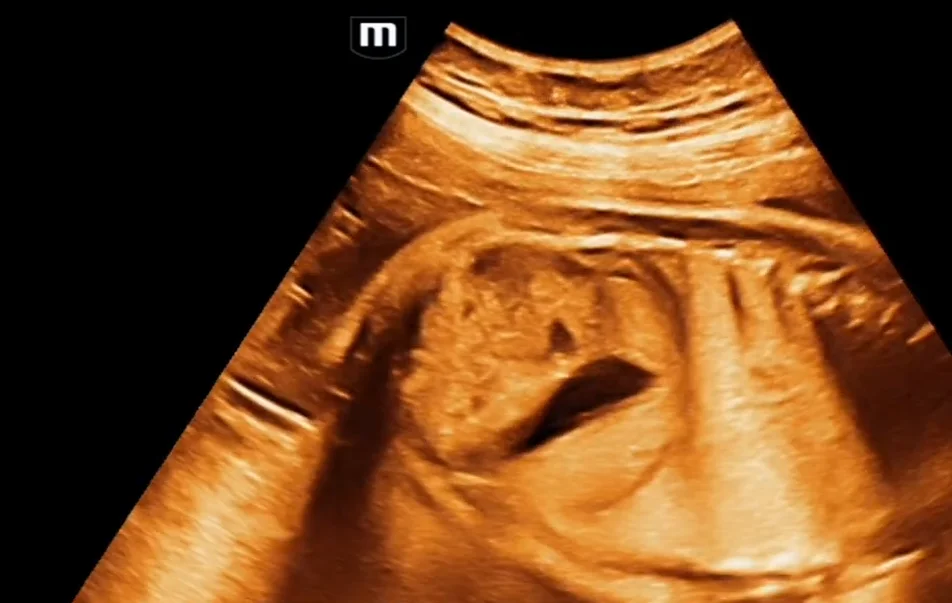

• Siêu âm Sản khoa

• Hệ thống tiết niệu thai

• Các biến thể phát triển của thận

• Bất sản thận một bên (Unilateral Renal Agenesis)

• Thận đôi - niệu quản đôi (Duplicated Collecting System)

• Thận lạc chỗ vùng chậu thai nhi (Pelvic Kidney)

• Thận móng ngựa thai nhi (Horseshoe Kidney)

• Thận lạc chỗ bắt chéo dính nhau ở thai (Crossed fused renal ectopia)